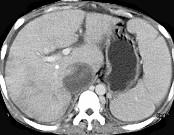

问题 女性,26岁,腹胀不适7月,腹软,肝右肋缘下1cm,影像检查如图,可能的诊断为 ( )

选项 A.肝血管瘤 B.原发性肝癌 C.肝硬化腹水 D.巴-希综合征 E.脂肪肝

答案 D